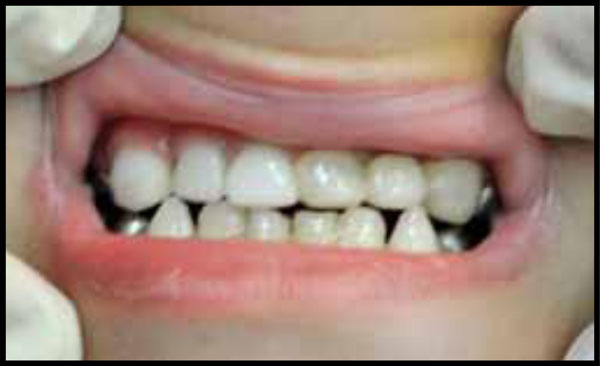

IM, severe ECC before treatment. Note the functional Class III occlusion.

Fig. (13).